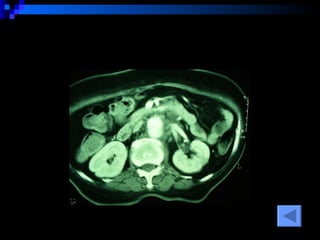

CT SCAN AAA juxtrareal -> bifurcation  Size 10*8*4 cm Inflamatory tissue  around AAA Intact renal artery Aortic dissection at juxtra renal -> bifurcation Bowel wall thickening at 3 rd -4 th  part of duodenum

CT SCAN AAAjuxtrareal -> bifurcation Size 10*8*4 cm Inflamatory tissue around AAA Intact renal artery Aortic dissection at juxtra renal -> bifurcation Bowel wall thickening at 3 rd -4 th part of duodenum